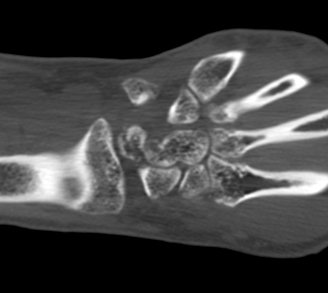

ÃÊÀ½ÆÄ°Ë»ç : ¼Õ¸ñ ¹èÃø Á¾´Ü¸é°Ë»ç¿¡¼­ ¼ö±Ù°üÀý³» ¼ö¾×Àú·ù°¡ °üÂûµÊ(»çÁø 1).

¼Õ¸ñ ÀåÃø Á¾´Ü¸é°Ë»ç¿¡¼­ ¿ù»ó°ñ °ñ±ØÀÌ °üÂûµÊ(»çÁø 2).